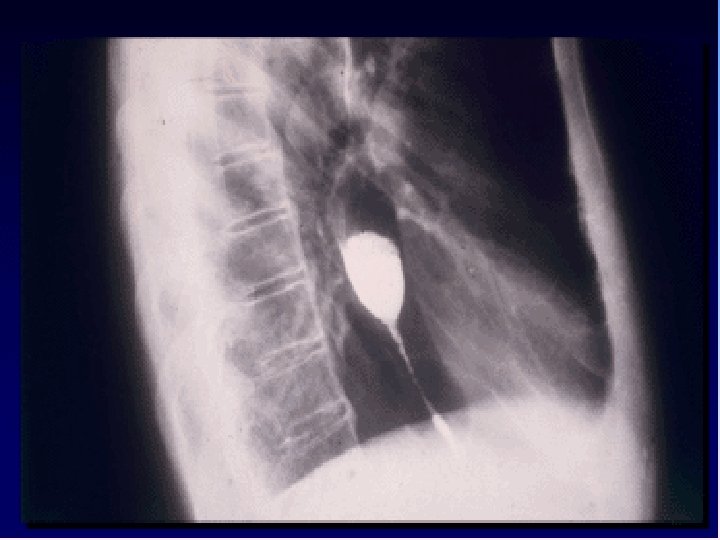

Case 3 • Middle age man is visited for evaluation of dysphagia to solids from 2 months duration. • He was a heavy smoker and used famotidine for heart burn for 14 y. • Ba swallow was performed. • Endoscopy and biopsy was done.

Proximal esophageal stricture

Peptic stricture